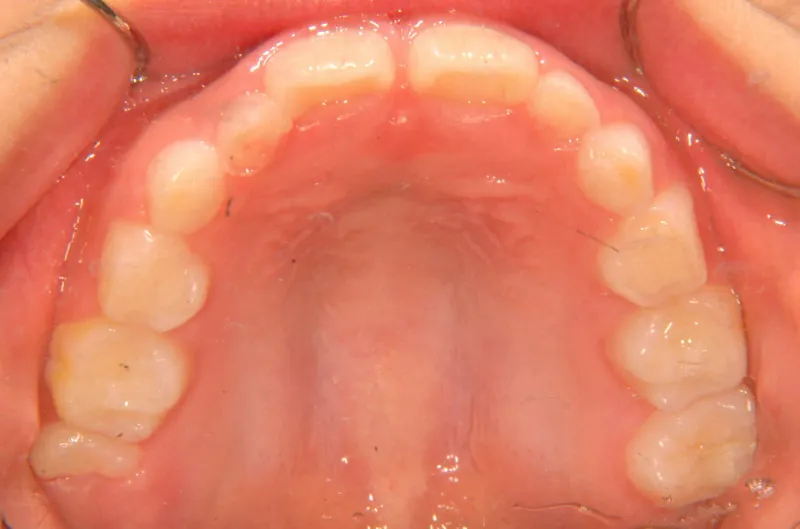

オリジナルの着け外しのできる装置で治療しました。

治療回数○回、4年7ヶ月の治療期間で矯正治療を終了しました。

1期治療で十分な結果が得られたと思います。

治療終了後